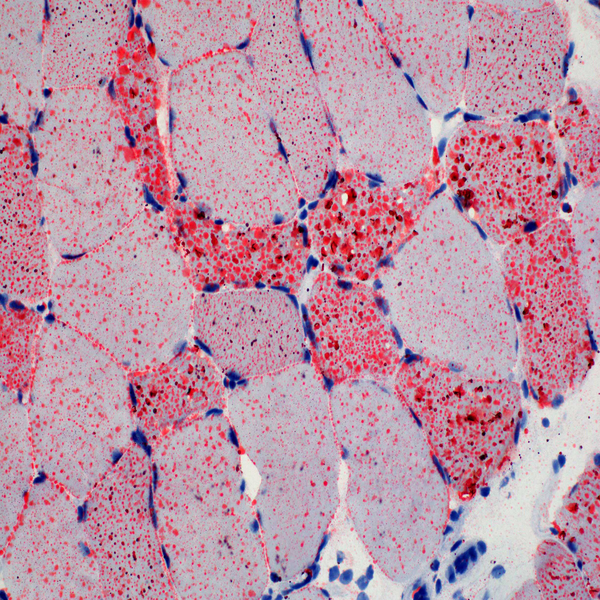

- General and specialized tissue and cell staining

Histological methods includes sample processing in the pathology laboratory, preparation of the slide and its examination under a microscope, sample fixation, molding, microtome cutting, staining and assembly of the slides.